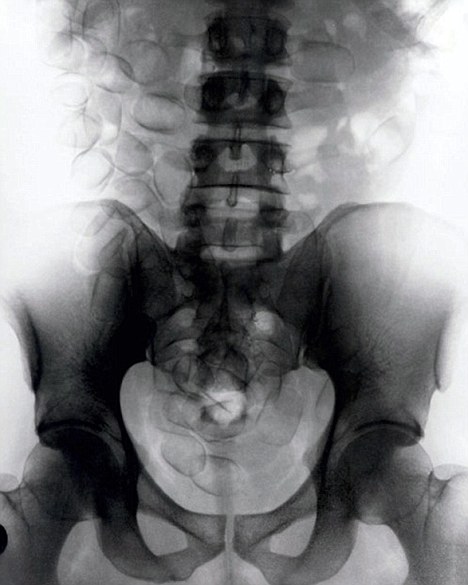

現(xiàn)年30歲的菲達(dá)利斯(Fidelis Ozouli)冒著生命危險(xiǎn)將重達(dá)1公斤的毒品吞下,被抓后卻辯稱不知道吞下的是毒品。當(dāng)時(shí),曼徹斯特機(jī)場(chǎng)的海關(guān)人員看到毒販菲達(dá)利斯臃腫的肚腩,顯得很不自然,于是開始懷疑。檢查人員用X射線機(jī)照他的胃部時(shí),發(fā)現(xiàn)了大量可卡因。目前他已被送往附近醫(yī)院,以確保排出所有的毒品。

這名男子還將毒品藏在幾十個(gè)避孕套里,估計(jì)純度為78%,價(jià)值25萬(wàn)英鎊。毒販后來(lái)被帶到曼徹斯特皇家法庭,自稱來(lái)自尼日利亞,目前在倫敦生活和學(xué)習(xí)。他承認(rèn)攜帶A類毒品入關(guān)確實(shí)犯了法,但否認(rèn)他吞下的是毒品。目前他已經(jīng)被英國(guó)警方正式逮捕,案件已轉(zhuǎn)交給毒品稽查部門,預(yù)計(jì)他將被判入獄10年。